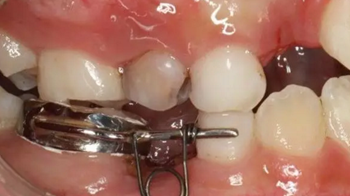

42、牙面拋光,試合制作好的間隙恢復(fù)器,將曲簧水平部分形成與牙面弧形一致,羧酸鋅水門汀粘結(jié)固定

43、粘結(jié)后的頰面觀

44、8周后復(fù)診間隙推開,自動變換為間隙保持器